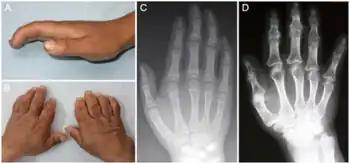

| a-d) Characteristics of child and adult Kashin-Beck disease individuals | |

Kashin–Beck disease (KBD) is a chronic, endemic type of osteochondropathy (disease of the bone) that is mainly distributed from northeastern to southwestern China, including 15 provinces.[1] Tibet currently has the highest incidence rate of KBD in China.[1] Southeast Siberia and North Korea are other affected areas.[1] KBD usually involves children ages 5–15. To date, more than a million individuals have suffered from KBD.[2] The symptoms of KBD include joint pain, morning stiffness in the joints, disturbances of flexion and extension in the elbows, enlarged inter-phalangeal joints, and limited motion in many joints of the body.[3] Death of cartilage cells in the growth plate and articular surface is the basic pathologic feature; this can result in growth retardation and secondary osteoarthrosis.[1] Histological diagnosis of KBD is particularly difficult; clinical and radiological examinations have proved to be the best means for identifying KBD.[4] Little is known about the early stages of KBD before the visible appearance of the disease becomes evident in the destruction of the joints.[4]